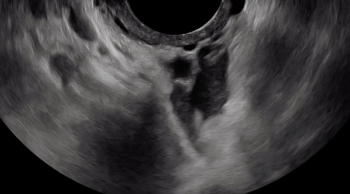

A hypoechoic deep endometriosis nodule is noted within the hyperechoic uterosacral ligament, infiltrating the parametrium

A hypoechoic deep endometriosis nodule is noted within the hyperechoic uterosacral ligament.